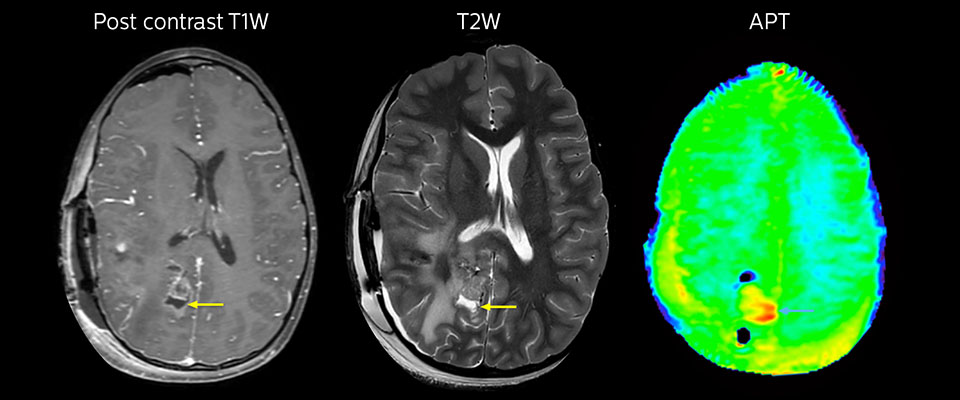

MRI may be performed after tumor resection, to look for residual tumor or tumor regrowth. Also here, the different contrast mechanism of APT may help in diagnosis. Dr. Miller remembers a particular case.

“After a very good resection, we saw small changes on the postcontrast T1-weighted and the T2-weighted images that looked like a post-surgical little bit of fluid. Interestingly, however, we saw a focal area of APT signal, right in the center of that abnormality. As we usually do when a bit unsure, we followed it up and, unfortunately, found tumor regrowth in that region,” Dr. Miller says. “Cases like this motivate me, and others who care about this population, to investigate how this APT method could be used on large scale in this population and help us in providing high value diagnostic information.”

The hospital’s physicians also saw a case where APT had a negative predictive value. Following the resection of a highgrade tumor, they saw a similar small change in the images of this patient. However in this case, the APT signal was rather low. In a recent rescanning of this patient, no recurrence was seen.

Immediately post resection MRI was again performed. T2-weighted and postcontrast T1-weighted images are quite inconclusive for distinguishing residual tumor tissue from postoperative tissue changes. On the APT image some high signal is still seen, which would suggest residual tumor tissue.